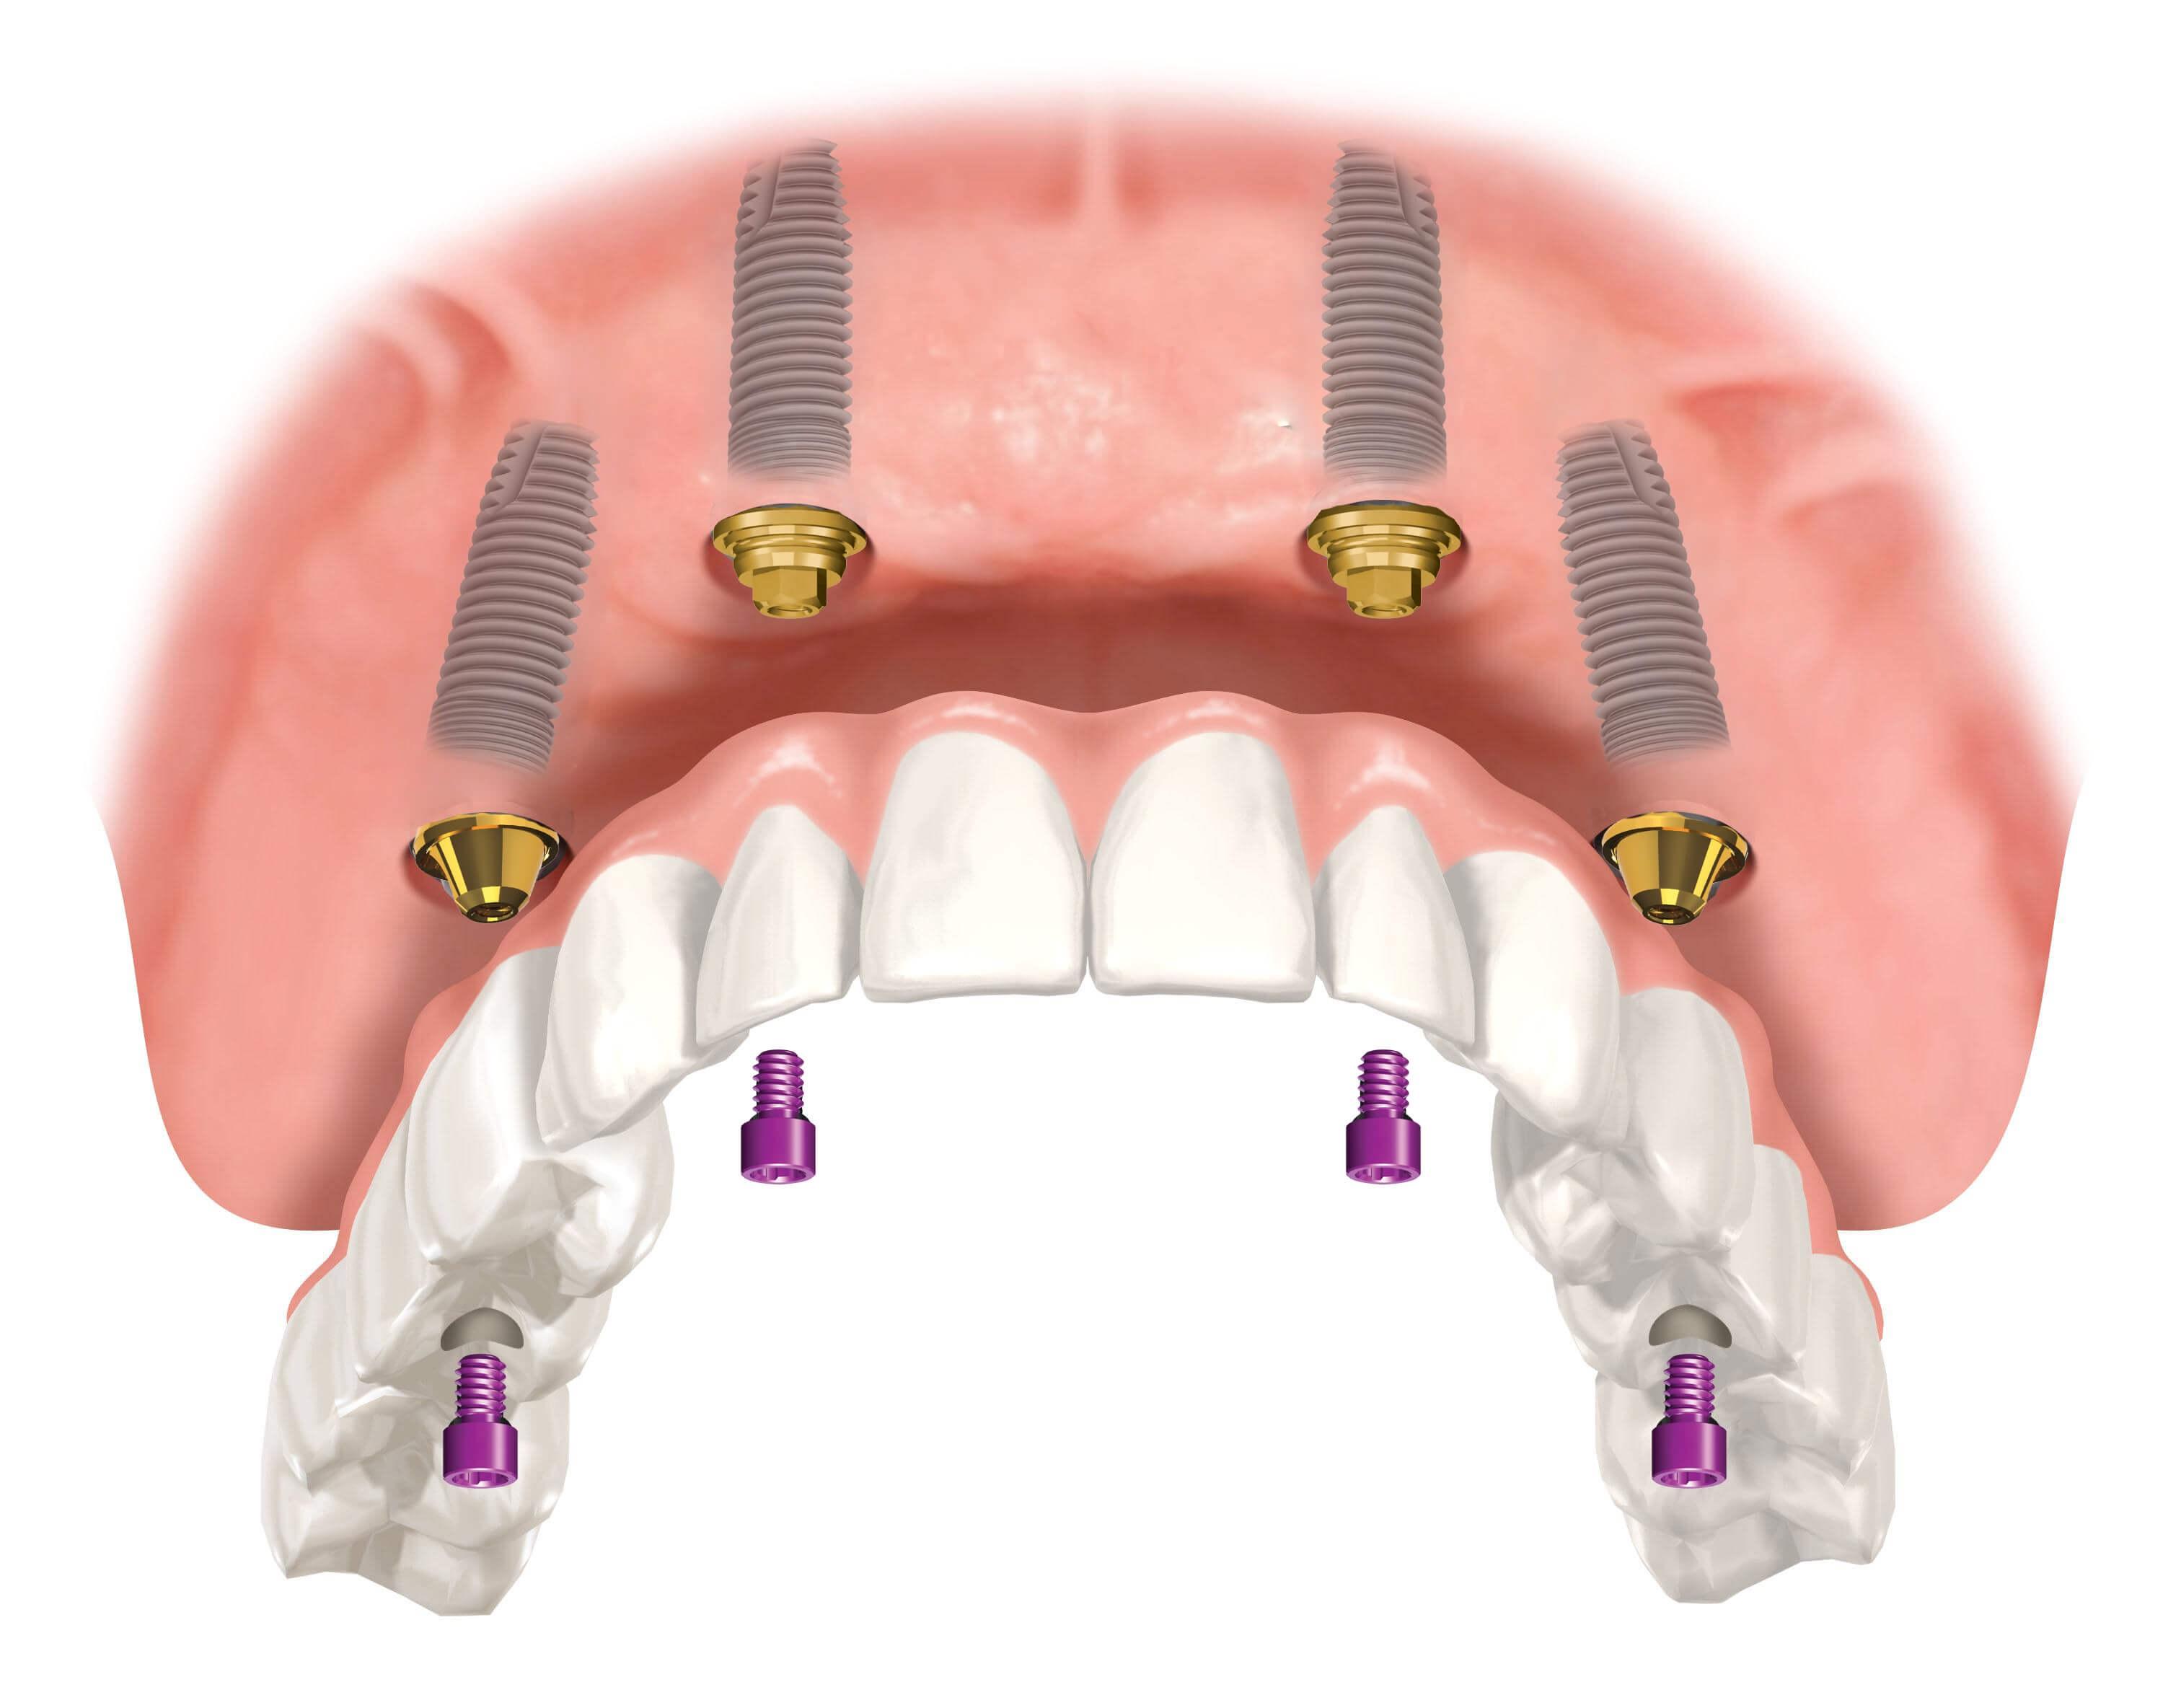

Современные съемные протезы на локаторах: Фото и примеры